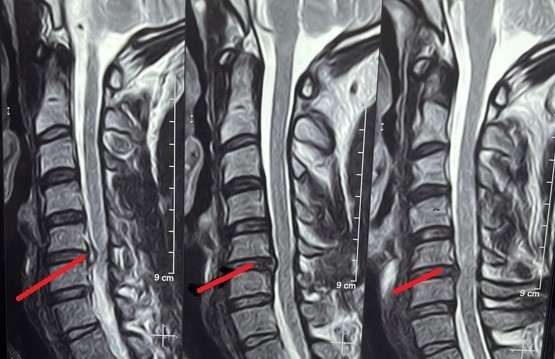

unilevel cervical herniated disc

Magnetic resonance imaging (MRI) of a 52-year-old female patient suffering from weakness and partial upper extremity weakness due to a herniated cervical disc between the fifth and sixth cervical vertebrae. As shown in red, the location of the slip and the size of the effect resulting from pressure on the cervical spinal cord and nerve roots. And the image shaded in green after a surgical microscope surgery to remove the cartilage from the front and install a cervical cage or an alternative anterior cervical brace, three months after the surgery.